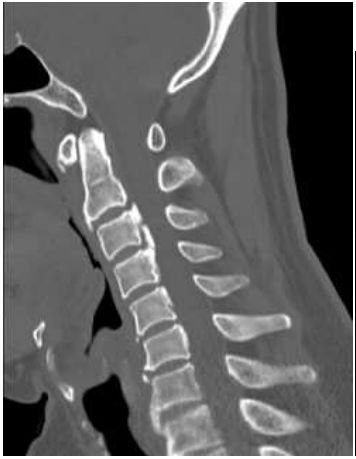

74.18 歲女性,因急性下腹痛就醫,腹部X光影像如圖,最可能的診斷為何?

(A)右髂內動脈瘤(right internal iliac artery aneurysm) (B)骨盆腔發炎性疾病(pelvic inflammatory disease) (C)畸胎瘤(teratoma) (D)薦骨骨折(sacral bone fracture)